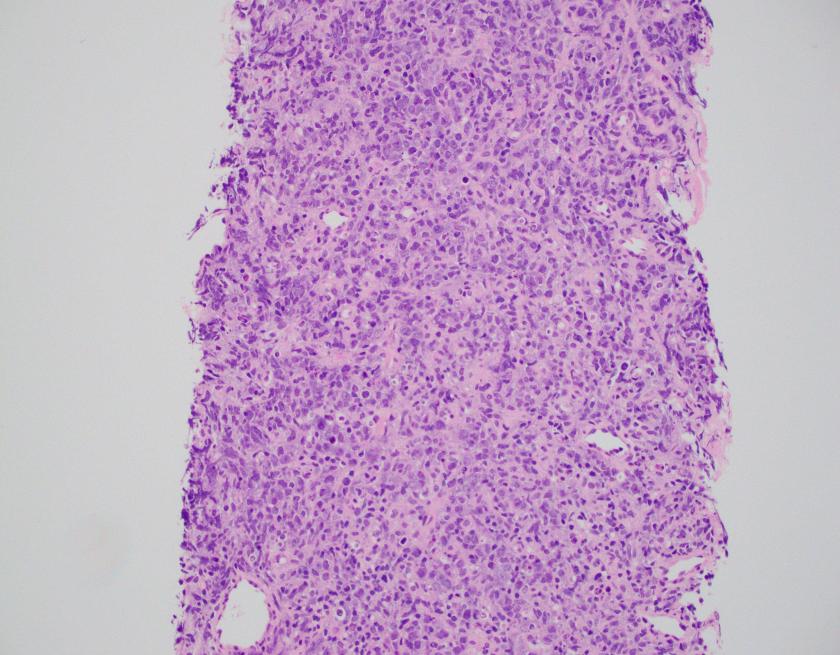

The CBC demonstrated severe anemia and mild leukopenia. The peripheral blood smear showed numerous acanthocytes and poikilocytosis shown below.

Acanthocytes, or spur cells, are spiculated red cells with a few projections of varying size and surface distribution that can be seen in a variety of clinical conditions including CGD with McLeod red cell phenotype. Other conditions include (but are not limited to) neuroacanthocytosis, malnutrition states, infantile pyknocytosis, (Lu) null Lutheran phenotype, hypothyroidism, myxedema, and Zieve syndrome. Acanthocytes should be distinguished from echinocytes, or burr cells, that also demonstrate multiple small projections but these are uniformly distributed on the red cell surface.

The prominent acanthocytosis seen in McLeod syndrome is thought to be due to an imbalance of the number of lipids in the inner layer relative to the outer layer. Related to this phenomenon is McLeod neuroacanthocytosis syndrome, a disorder with neurologic manifestations including movement disorders, cognitive alterations, and psychiatric symptoms. Although our patient did not exhibit these symptoms, McLeod neuroacanthocytosis syndrome is known to start in early to middle adulthood and the patient will need to be monitored for the onset of neurologic sequelae.